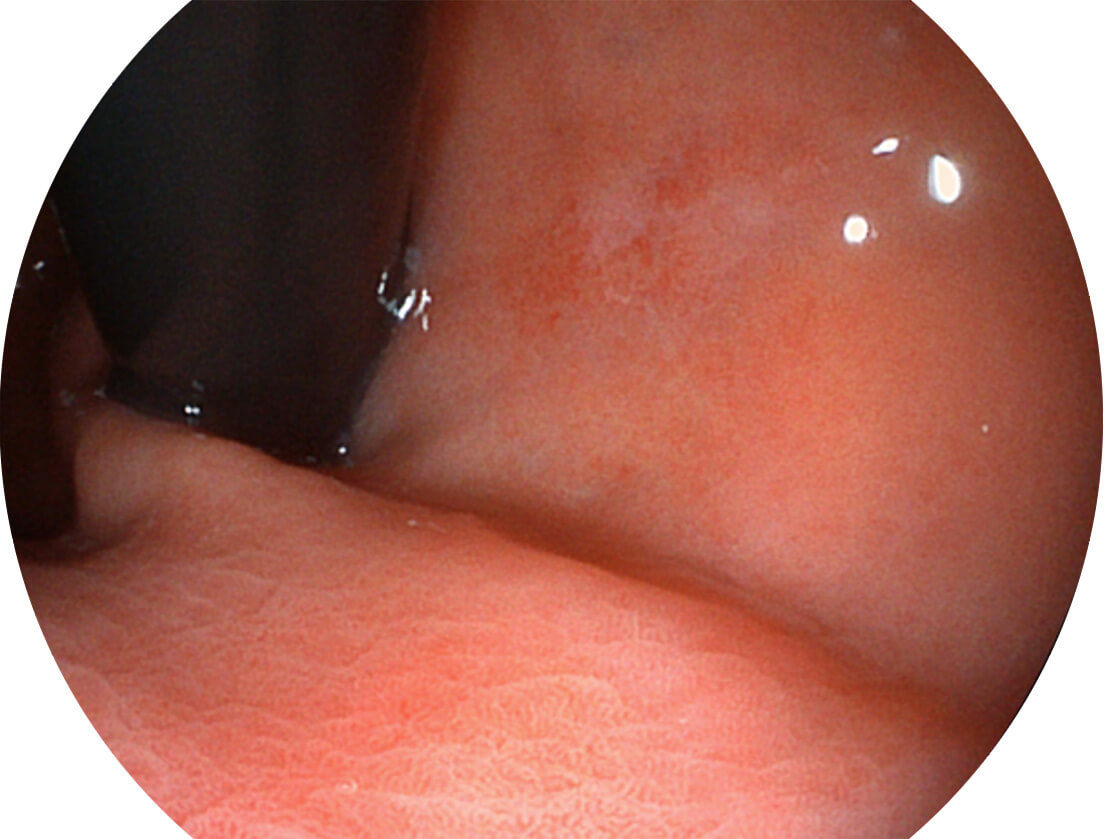

图像具有高亮度、高黏膜血管颜色对比度的特点,且不改变粘液、食物残渣、粪便的基本颜色,可在中远景下进行观察,助力消化道早期疾病的诊断。

强调浅层黏膜结构的同时,保证照明亮度和提升浅层微血管与中层血管颜色对比度,病变边界更清晰。